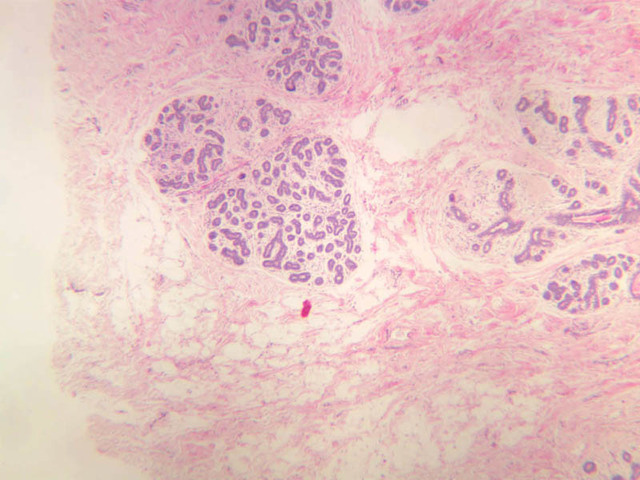

The resting or inactive mammary gland consists of predominantly dense connective tissue with small clusters of ducts and a few glandular elements (slide A-93 [2.5x-labeled, 10x, 20x, 40x] [1x, 2.5x, 10x, 20x]). It is difficult to differentiate between small ducts and alveoli as each is lined by simple low cuboidal cells. Lobes and lobules are not well defined. During puberty, predominantly under the influence of the ovarian hormone estrogen, the glandular or epithelial ducts proliferate and begin to differentiate into clusters of ductal and alveolar units termed terminal ductal lobule units (TDLUs). The non-pregnant gland will form multiple TDLUs that will not fully differentiate until pregnancy-induced growth. TDLUs are classified into Type I, Type II and Type III based on density of the ductules within each lobular unit. Type I and Type II lobules are typical of inactive glands that have not undergone a pregnancy cycle. Type III lobules are seen only in active glands or in inactive glands that have been through a pregnancy. Intralobular connective tissue is loose connective tissue that surrounds the alveoli and ducts within a lobule. The interlobular connective tissue is dense and contains considerable adipose tissue.

During pregnancy, predominantly under the influence of the ovarian hormone progesterone and the pituitary hormone prolactin, the glandular elements proliferate and differentiate to form milk-secreting units. In later stages of pregnancy, alveolar development becomes prominent and the amount of connective tissue and adipose tissue decreases. The secretory cells hypertrophy and accumulate secretory product.

The mammary gland in its active state is a compound tubuloalveolar gland (slide A-92 [10x, 20x, 40x-labeled] [2.5x, 10x, 20x, 40x]; A-94 [2.5x, 10x, 20x, 40x]). At this time, the gland is predominantly glandular tissue. Each alveolus is lined by a simple cuboidal epithelium. At the base of these cells, and within the alveolar basal lamina, are the stellate-shaped myoepithelial cells that are highly contractile and function to facilitate milk ejection.